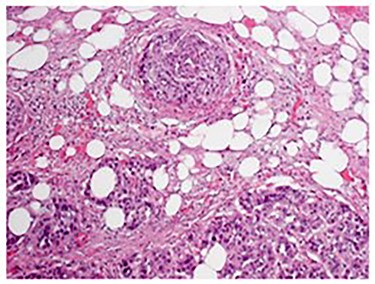

Pathologic analysis revealed an AJCC Stage IV (pT3, N0, M1) 7.7 cm moderately differentiated (histologic grade G2) adenosquamous carcinoma of the gallbladder with lymphovascular and perineural invasion, and tumor extension into adjacent liver, peritoneal surface and residual lesser omentum. Surgical margins were all negative. No tumor was identified in any of the eight portal lymph nodes obtained. Figure 6 shows a gross cross section of the gallbladder. Figure 7 shows H&E stain of the tumor demonstrating adenosquamous features. Figure 8 shows an H&E stain demonstrating peritoneal surface involvement. Figure 9 shows an H&E stain demonstrating involvement of the lesser omentum.